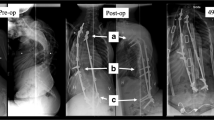

Mean preoperative major coronal curve magnitude was 73° (range 37°–128°) and mean global kyphosis was 45° (range 18°–74°). The majority of patients were treated with TGR and underwent a mean of 10.3 surgeries, including 7.5 lengthenings and 2.7 revisions (Table 2). Mean GPI spanned 12.3 segments (range 8–17 segments), including 10.7 motion segments (range 5–17segments). Six patients underwent some form of vertebral resection and four underwent thoracoplasty for fused ribs (Table 2). Final fusion was performed in 24 patients, and two concluded treatment with GPI left in place: 1 with spine-based TGR and 1 with a Shilla construct. Figures 1, 2 and 3 demonstrate representative radiographs of patients 9, 17, and 22, respectively.

a PA and lateral preoperative standing radiograph of patient 9, a 3.3-year-old boy without associated diagnoses, demonstrating a 90° coronal curve, 13.5 cm T1-T12 height, 4.9 cm positive sagittal balance, and 2.3 cm coronal balance. b PA and lateral postoperative radiographs following placement of GPI at 3.6 years of age using a Shilla procedure from T2–L3 (13 levels, 9 motion segments due to fusion of T2–T3, T8–T10, and L2–L3) demonstrating a 21° coronal curve, 18.2 cm T1–T12 height, 1.4 cm positive sagittal balance, and 2.9 cm coronal balance. c PA and lateral standing radiographs at final follow-up (11.7 years of age) with instrumentation T2–L3 demonstrating a 38° coronal curve, 17.3 cm T1–T12 height, 2.5 cm positive sagittal balance, and 1.0 cm coronal balance